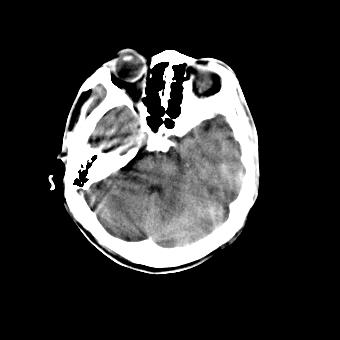

标题: CT16478:男 头晕 恶心 呕吐 [打印本页]

标题: CT16478:男 头晕 恶心 呕吐

病人不合作,图像质量差,右额叶及后纵裂可见高密度影,建议复查。

1.额叶显示密度不均匀,且右侧内见小片稍高密度影, 图像效果差些,不好定?

2.纵裂密度增高,部分脑回密度似乎也增高,蛛网膜下腔出血。

右额叶小片状高密度灶,周围有水肿带,为脑出血;是否有外伤史?若没有,则考虑肿瘤——胶质瘤出血可能性大。

病人不合作,图像模糊,大脑镰及纵裂池后部密度增高;考虑:蛛血?

右额叶片状低密度灶,其前内侧小片状略高密度,首先考虑胶质瘤

另外恶心呕吐多久,临床有无发热,年龄多大?不排除脑炎的可能

[quote]以下是引用叶子123在2008-11-13 9:55:00的发言:[br]患者因煤气中毒入院,临床及ct均诊断一氧化碳中毒性脑病[br][br]